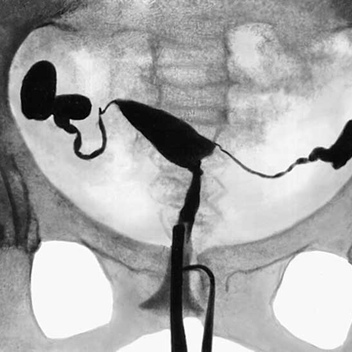

Чтобы проверить проходимость и состоятельность труб матки проводится гистеросальпингография. А чтобы проверить состояние матки, то проводится гистероскопия. Если требуется удалить какую-либо причину в матке, например, кисту, то проводится лапароскопия. Удаляется интересующий элемент в матке. Если есть наличие спаек, то можно эти же способом их разъединить.

Рентген маточных труб на проходимость

Рентген маточных труб на проходимость. Современные женщины даже несмотря на высокую просвещенность в области репродуктивных технологий и других медицинских нововведений опасаются и…